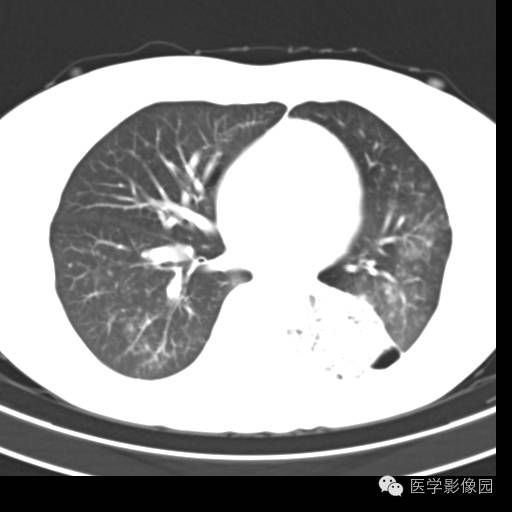

肺叶实变性支气管肺泡癌1例CT影像表现